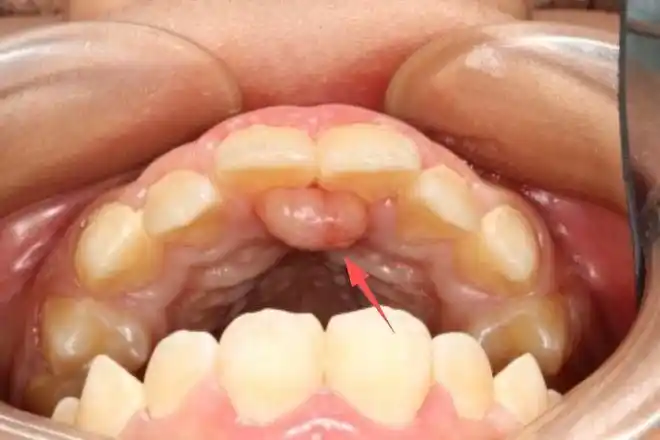

孩子牙龈鼓包,除了是马牙,还可能是这5种疾病